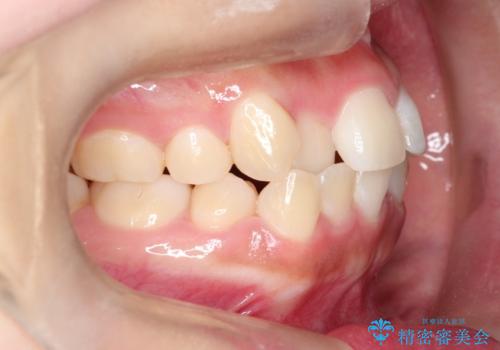

奥歯の噛み合わせは綺麗に噛んでいたため、前歯の叢生(でこぼこ)を、短期間で治療完了するように計画しました。

前歯のガタツキを改善する治療法として、マウスピース矯正が適していることが多いです。